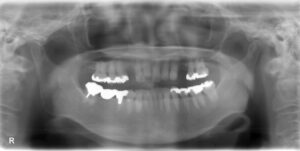

上下臼歯9本欠損症例

BEFORE AFTER 74歳女性/上下9本欠損/インプラント埋込手術 【治療内容】 根っこの先で炎症が広がり抜歯とな…